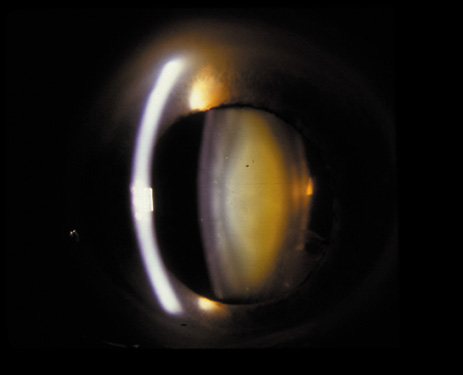

Nuclear cataracts tend to progress slowly. The refractive index of the lens changes as the nucleus progressively hardens, which usually results in increasing myopia.20,21 In some patients this is accompanied by optical distortion, especially of distant images, while near vision remains unaffected. A nuclear cataract is best seen with the narrow-beam direct illumination employed by the slit-lamp, which reveals the color and generalized haze or opalescence of the nucleus. In the early stages, the two halves (cotyledons) of the embryonic nucleus remain visible (Fig. 3). Later the entire nucleus appears as a homogeneous mass in contrast to the cortex (Fig. 4). Retroillumination may show the “oil droplet” effect (Fig. 5). Sometimes one may notice crystals in the lens nucleus (known as a Christmas tree cataract; Fig. 6A and B).

Fig. 3. Early nuclear cataract. Note the “cotyledons” in the nucleus.

Fig. 4. Advanced nuclear cataract. Note the homogeneous nuclear opacity.

Fig. 5. “Oil droplet” appearance of a pure nuclear cataract seen on retroillumination examination.